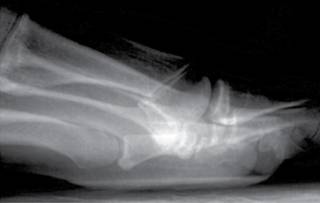

El paciente se colocó en decúbito supino bajo anestesia regional del pie y control por medio de fluoroscopio; se realizó primero la sección del ligamento intermetatarsiano con una hoja de bisturí 67 MIS, mediante una incisión longitudinal en el espacio intermetatarsiano a nivel del cuello (Figura 2), apoyándose sobre el cuarto metatarsiano, deslizándose sobre la cortical lateral con dirección inclinada de proximal hacia distal, se profundizó con la parte cortante hacia los dedos y con un movimiento de abajo hacia arriba se seccionó el ligamento intermetatarsiano transverso, percibiéndose el corte debido a la resistencia que se produjo en dicho acto.

El segundo gesto quirúrgico consistió en hacer osteotomías del tercer o cuarto metatarsiano usando dos incisiones a nivel del cuello, con la misma hoja de bisturí y a nivel del pliegue interdigital dorsal; con una raspa pequeña se disecó el periostio de la cara lateral del cuello del tercer metatarsiano y se hizo un canal a la vez; posteriormente, se introdujo una fresa Isham larga o Shanon 44 larga con una inclinación de 45º, se inició la osteotomía con una dirección oblicua de distal dorsal a plantar proximal (Figura 3). La osteotomía del cuarto metatarsiano se realizó de la misma forma. Se suturaron las heridas con nylon 3-0, se colocó un vendaje con gasas interdigitales de lateral a medial del segundo, tercer y cuarto espacios para estabilizar las articulaciones metatarsofalángicas; para finalizar, se puso un zapato postquirúrgico de suela rígida, que permitía el apoyo inmediato sin asistencia.